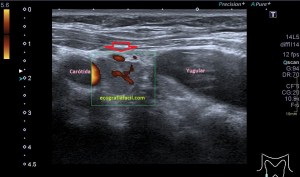

Con la eco pasa igual…cuando queremos estudiar, por ejemplo, el recto anterior del muslo en axial,perfecto…pero en longitudinal, como la imagen 2, se complica porque desde la rótula a la inserción en la cadera, tenemos mucho recorrido. En este caso hacemos lo mismo que cuando hacemos la foto del atardecer…nos ponemos en un extremo, activamos la funciona, recorremos suave y continuamente por la anatomía que queremos fotografiar y ya está…mira la pantalla y no el movimiento de tu mano,como si hicieses la foto, ves la pantalla,pero no como mueves el teléfono.